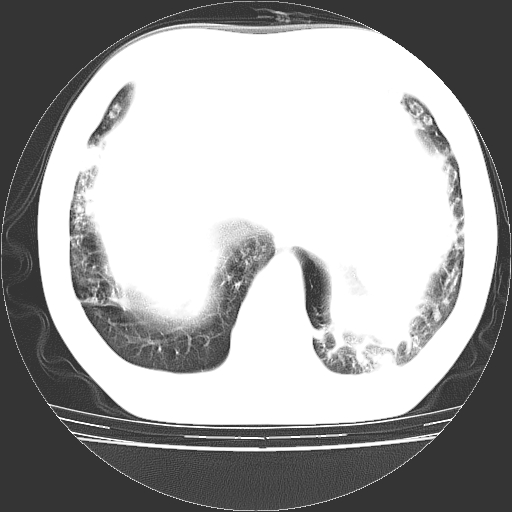

以下是引用zyx168在2006-12-4 15:30:00的发言:[br]经典!支气管肺囊肿并感染。

以下是引用dyqct在2006-12-4 17:11:00的发言:[br]典型的囊状支扩合并感染。

以下是引用liaoqiang在2006-12-4 16:12:00的发言:[br]局部肺叶内可见扩张的支气管壁,考虑为支扩。部份囊样影内有小液平和肺内散布斑片征影、小结节及纤维灶,提示支扩伴感染,且由于局部呈现有树芽征感染以结核可能性大。

以下是引用zhoucan076在2006-12-4 16:48:00的发言:[br]囊状支扩合并感染